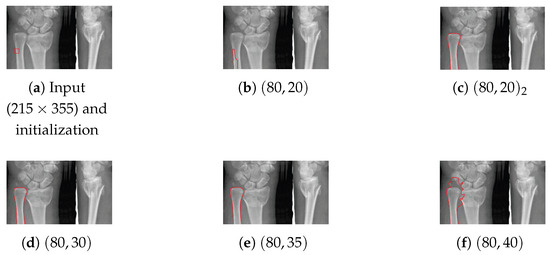

There are several drawbacks in the existing localization (active contour) models. Some models have poor capability of handling uneven illuminations and low contrasts, others are sensitive to initial condition, and there are still some models which can not converge to the object boundary stably. In this paper, following the routes of Localizing Region-Based Active Contours (LRBAC) which is an important localization method, we propose a new localized active contour model. By altering the underlying construction logic, our proposed algorithm overcomes the problem of LRBAC with respect to poor convergence stability. Compared with some state-of-the-art localization models, our new algorithm is more similar to an edge-based one and therefore performs better when handling uneven illuminations and low contrasts. Moreover, combining the features of the region-based and the edge-based active contours, we propose, for our algorithm, a simple approach to dynamically control the localization size. This dynamical method makes our algorithm more robust to the initial condition. Detailed theoretical analysis and comparison are presented to clarify the features of our proposed algorithm. Experimental results on real-image segmentation underline the effectiveness of our proposed algorithm. Full article

Show Figures

Figure 1